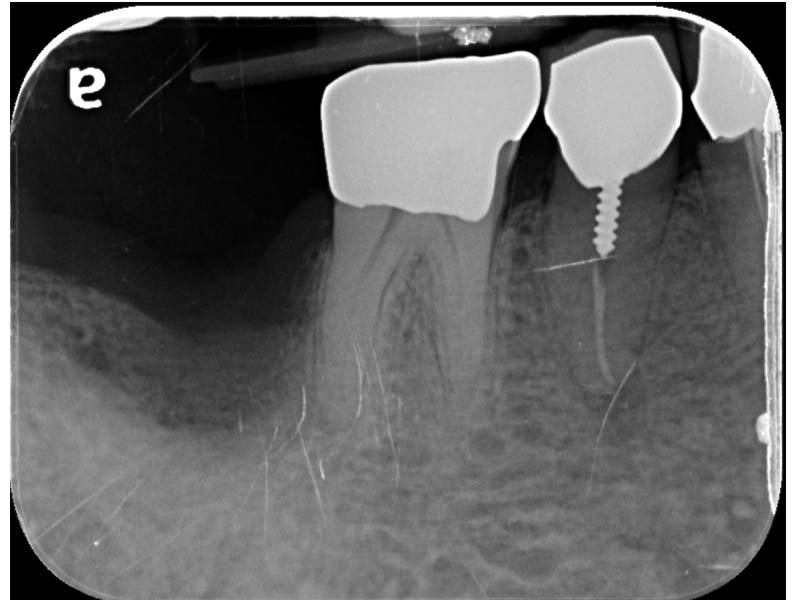

圖例為案例分享:

術前

帳棚釘+骨粉+再生膜術後6個月

植牙術後5.5個月